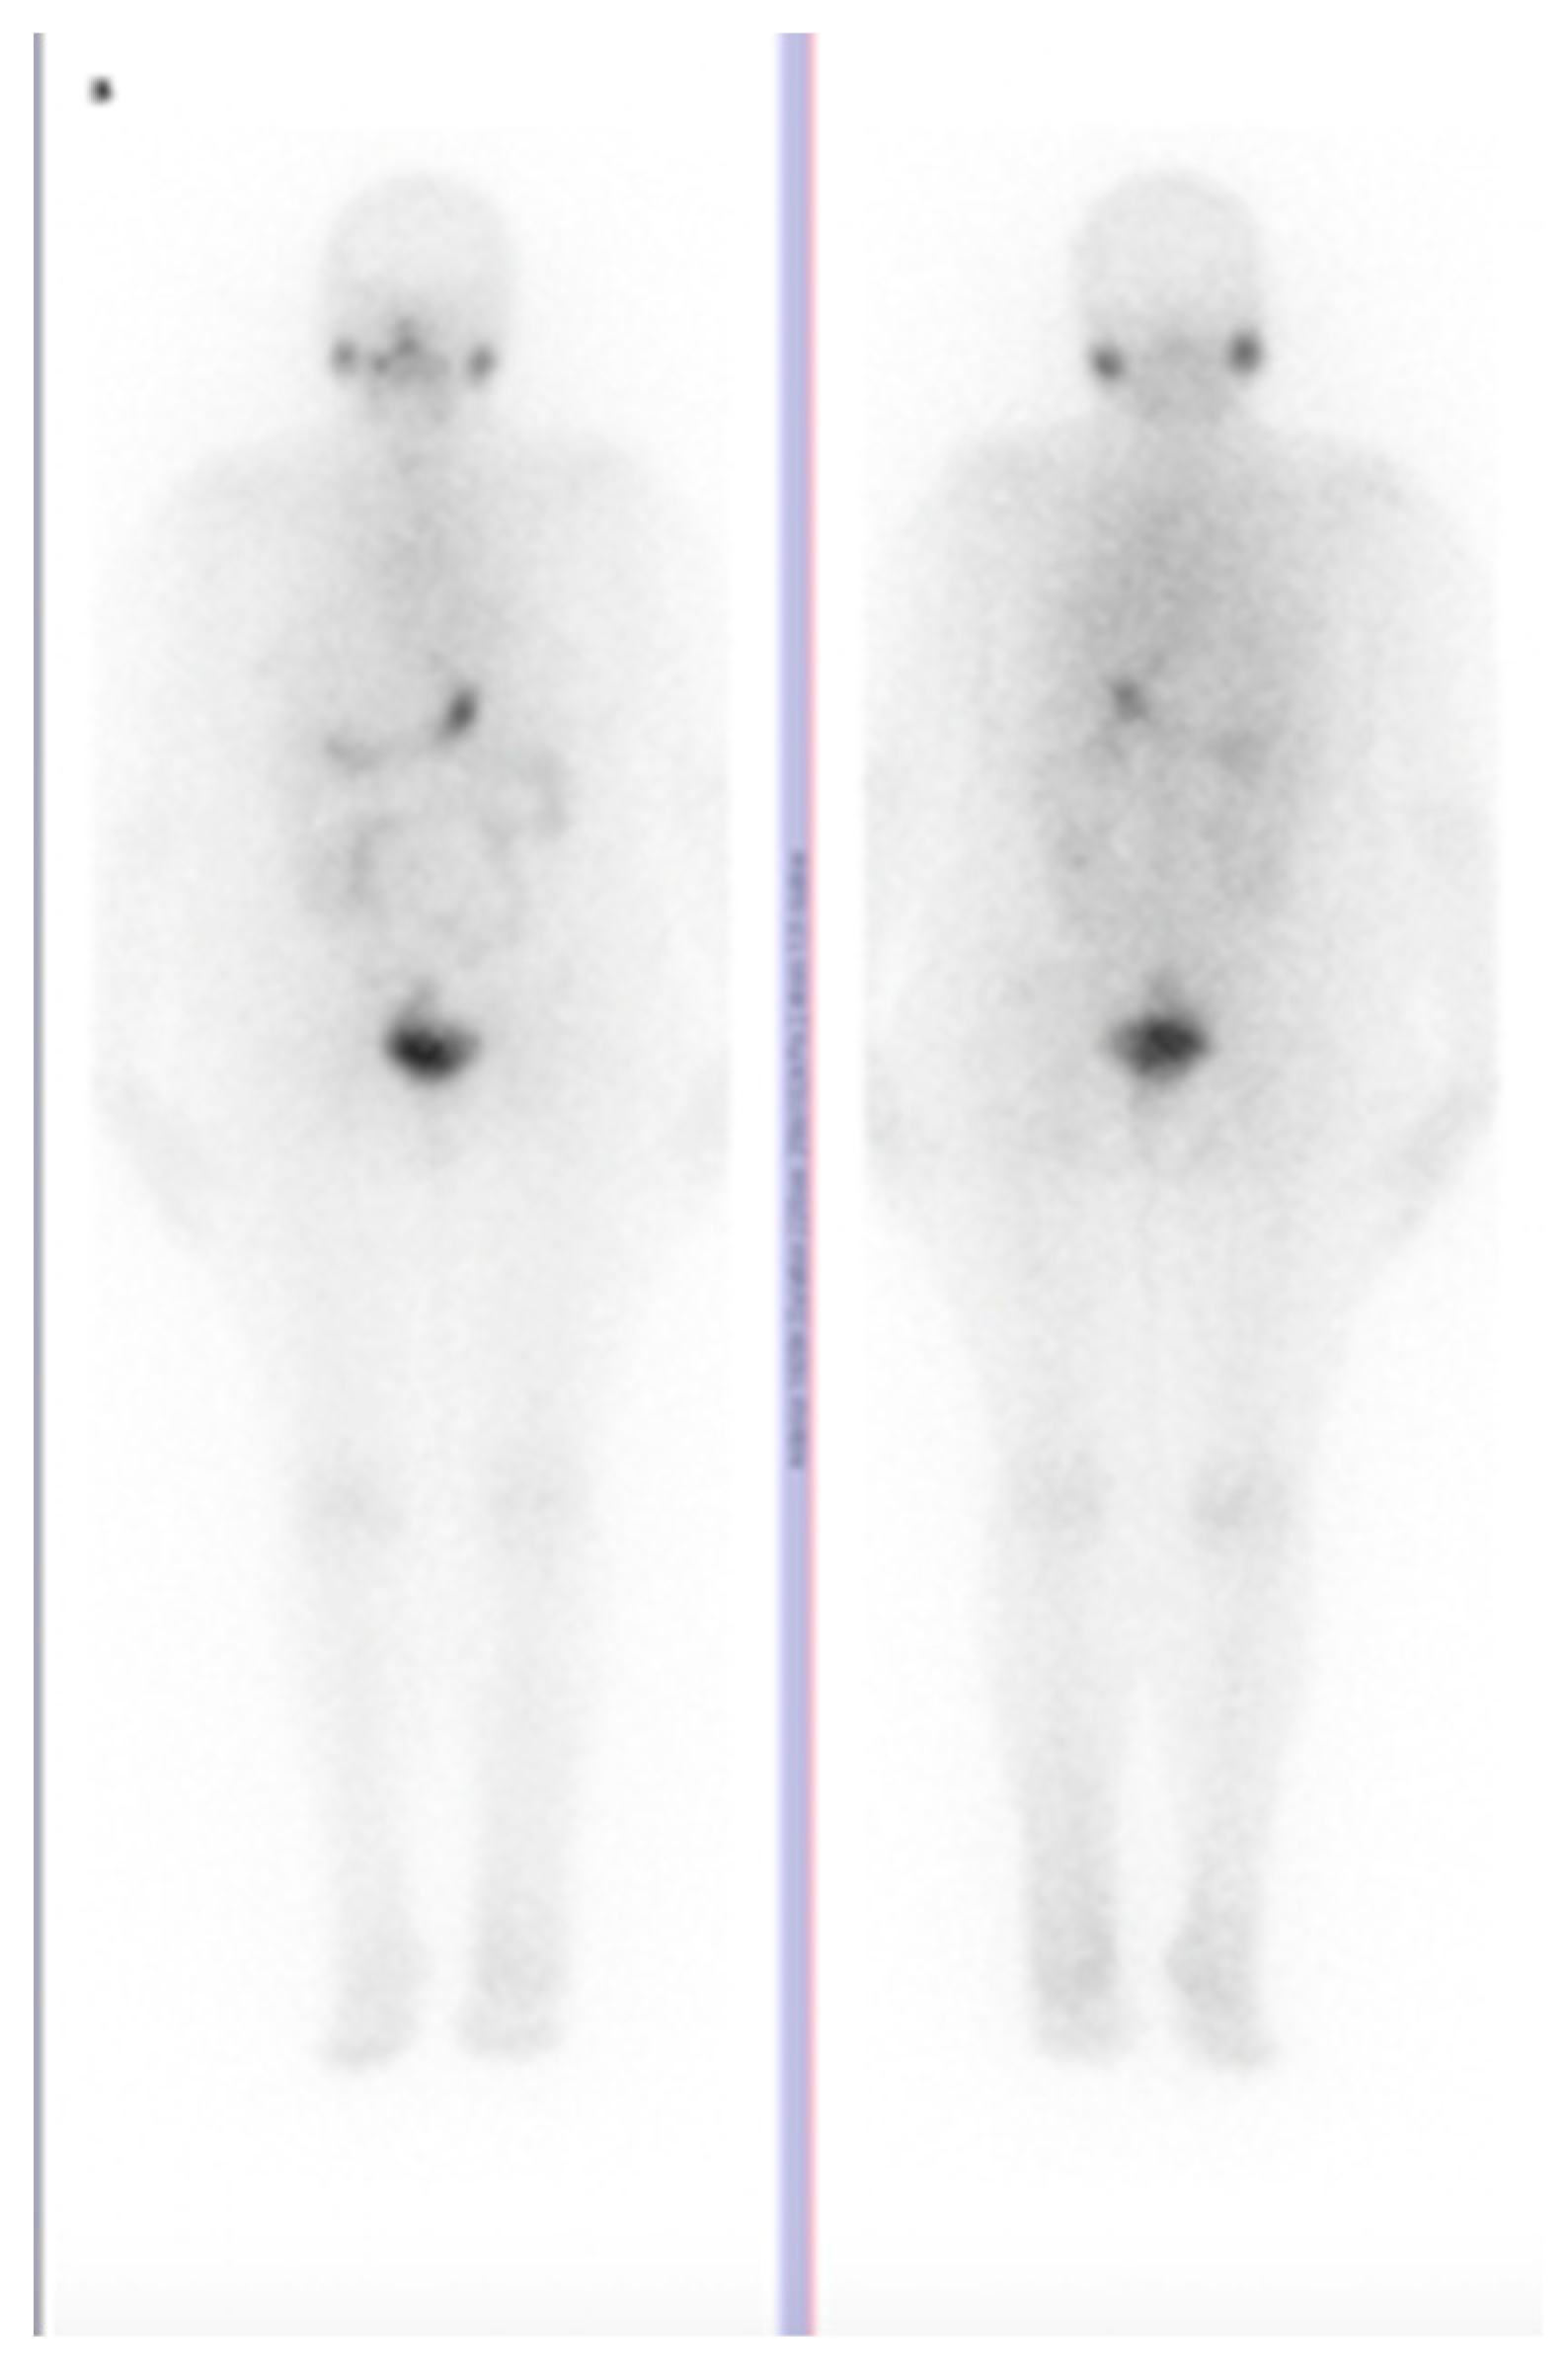

Skeletal Muscle Metastasis in Papillary Thyroid Microcarcinoma Evaluated by F18-FDG PET/CT